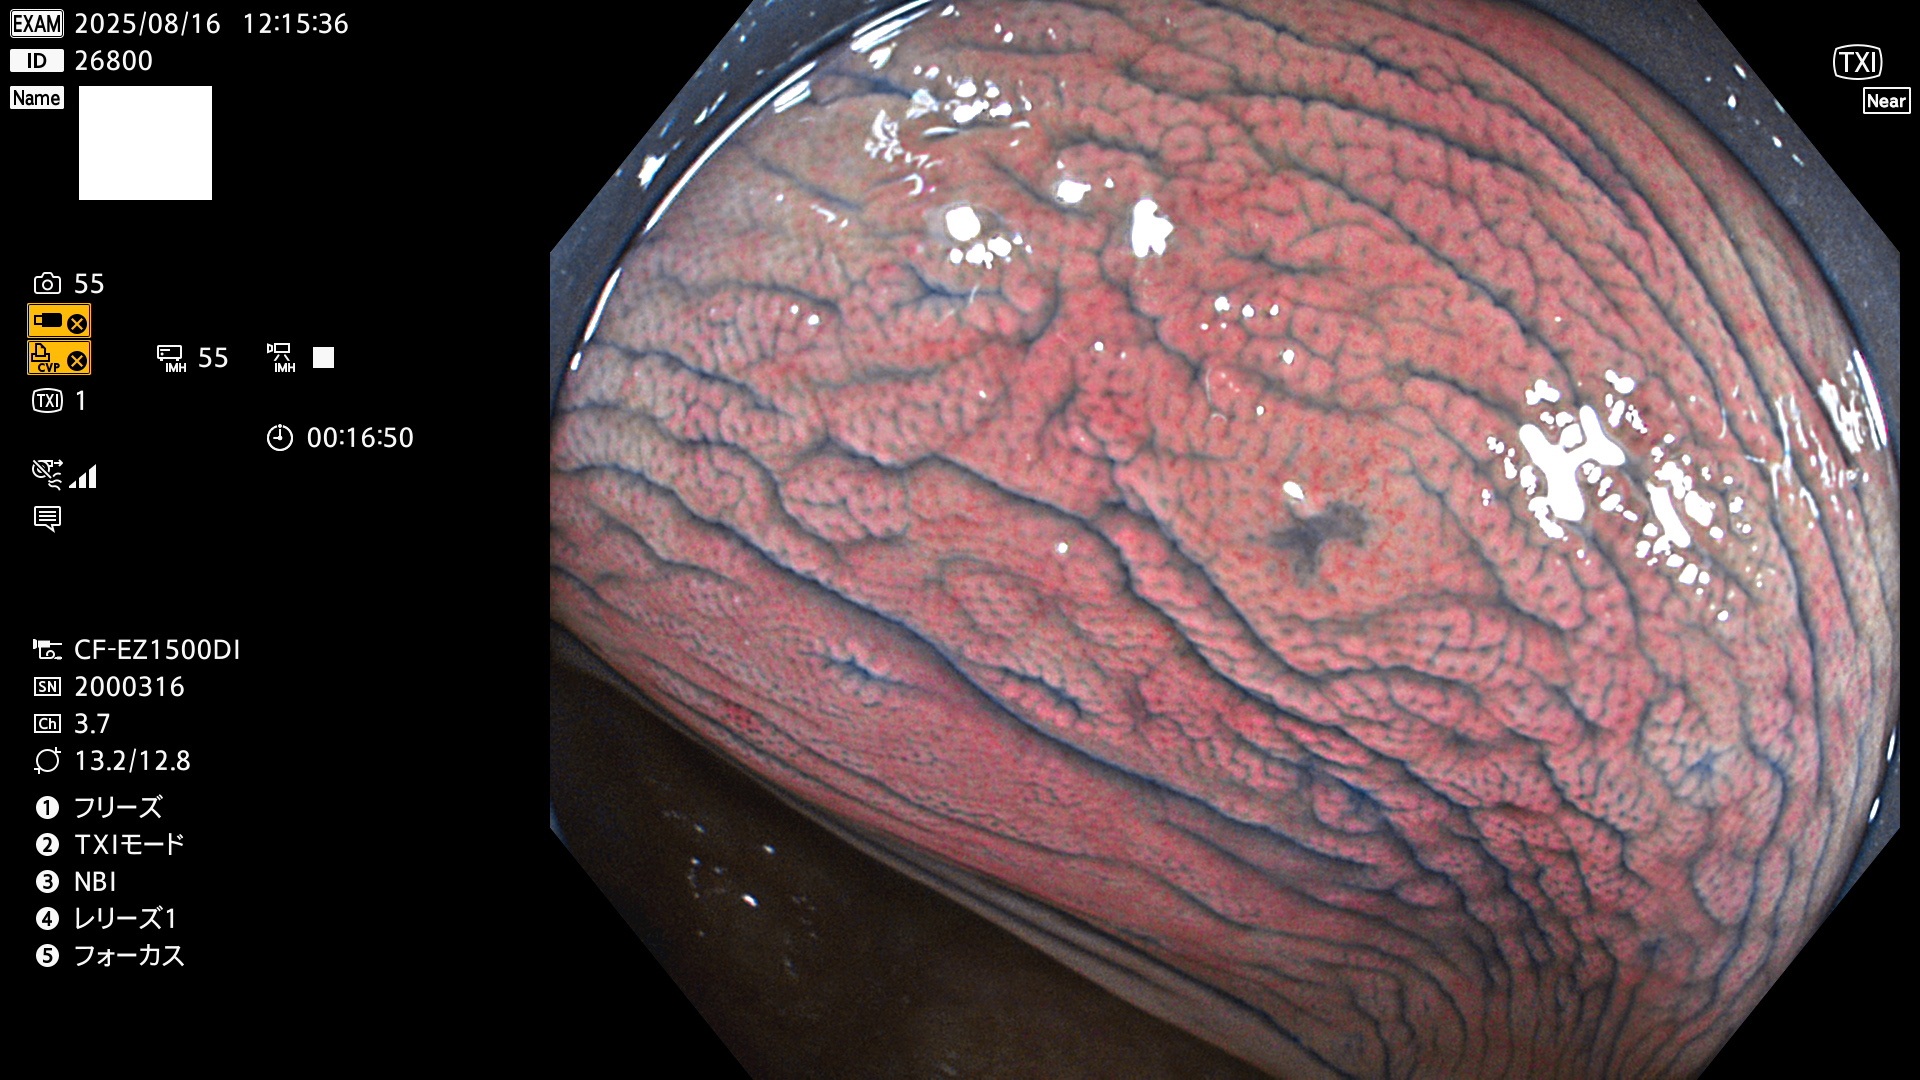

完全に平坦な物をUb、陥凹している物をUcと呼びます。Ubは認識が困難で、Ucはびらん(炎症)と紛らわしいために見落とされやすく、「内視鏡後・大腸癌」の原因になります。

専門的)Uc=De Novo癌? 内視鏡の解像度が低かった時代、このような説もありました。しかし今日の高精度内視鏡では良性の微小なUc型腺腫(APC遺伝子異常の腺腫)が日常的に見つかります。Ucこそが多段階発癌(Adenoma-Carcinoma Sequence)のMain Routeです。

2025年8月14日〜8月17日の4日間(30件)3個 (Uc_ADR=3個/30人=10%)